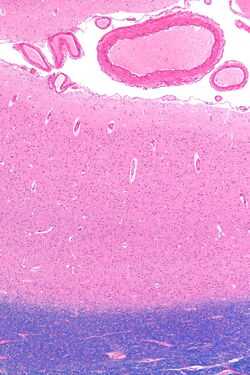

Рис.5.Микрофотография показывает зрительную кору (розовый цвет). В pia mater и паукообразные в том числе кровеносные сосуды видны в верхней части изображения. Подкорковое белое вещество (синий) - это видно в нижней части изображения. ОН-LFB пятно..

Первичная зрительная кора — наиболее изученная зрительная зона мозга. Исследования показали, что у млекопитающих она занимает задний полюс затылочной доли каждого полушария (эти доли ответственны за обработку зрительных стимулов). Это наиболее просто устроенная [6] и филогенетически более «старая» из кортикальных зон, связанных со зрением. Она приспособлена для обработки информации о статических и движущихся объектах, в особенности, для распознавания простых образов .